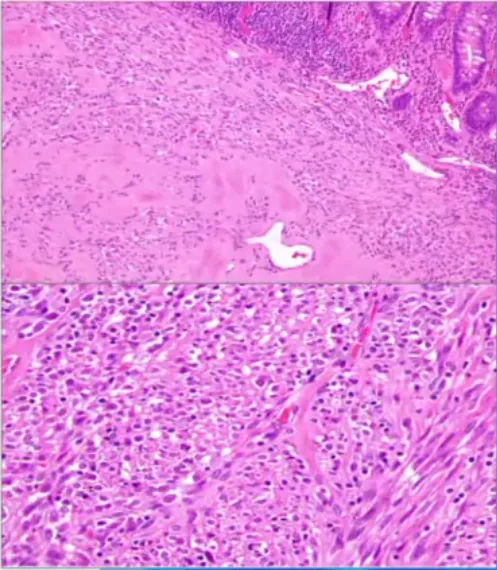

NUT重排肉瘤新增

• 定义:以NUT基因重排为特征的高度侵袭性肿瘤。

• 发病与部位:极罕见,全球报道〈45例消化道受累16例:食管2、胃4、小肠1、结肠9;

• 临床特征:几乎均为女性(15/16,94%);

• 病因与发病机制:常见融合:MXD4:.NUTM1、MXI1:NUTM1等,涉及15号染色体NUTM1基因;

• 镜下:梭形细胞、上皮样/横纹肌样细胞,玻璃样变背景,核分裂易见;

• 免疫组化:NUT阳性,少数表达角蛋白,SMARCB1/SMARCA4保留;

• 预后:胃肠道病例预后差,多数出现转移。